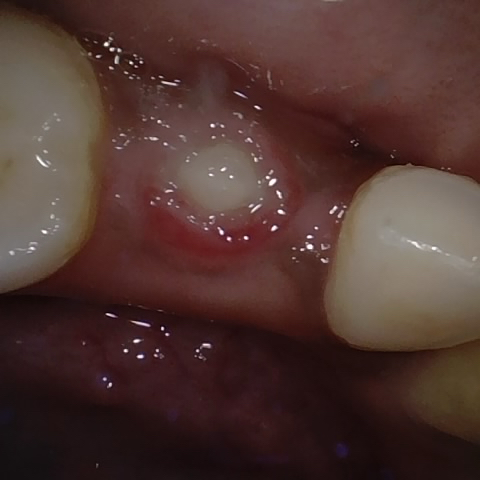

Annotated as "Good"